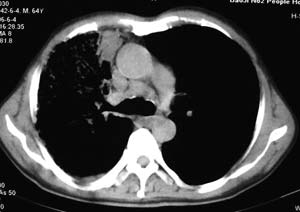

右侧胸廓略小于左侧,右肺上叶大片实变影,近肺门处密度较高,内见支气管气相,周围较淡,呈网格状,余肺野清晰,纵隔内见肿大淋巴结,右侧胸腔少量积液。临床 咳血,咳痰 发热 , 血象1.2万。

考虑大叶性肺炎。

右侧胸阔塌陷,纵隔右移。右上肺大片状高密度影,沿支气管血管束走行,内见点状钙化;支气管充气征阳性,支气管呈柱状扩张;胸膜下小叶间隔增厚;右侧后胸壁内侧见带状水样密度影;纵隔淋巴结增大。

考虑:①右上叶陈旧性结核合并感染可能大。②右侧少量胸水。

男 64  咳血,咳痰 发热 3天 血象1.2万;右肺上叶满布片絮状致密灶,其内见含气支气管影,右主支气管狭窄,纵隔内见肿大淋巴结。考虑右肺中央型肺癌伴阻塞性肺炎,建议支气管镜检查。